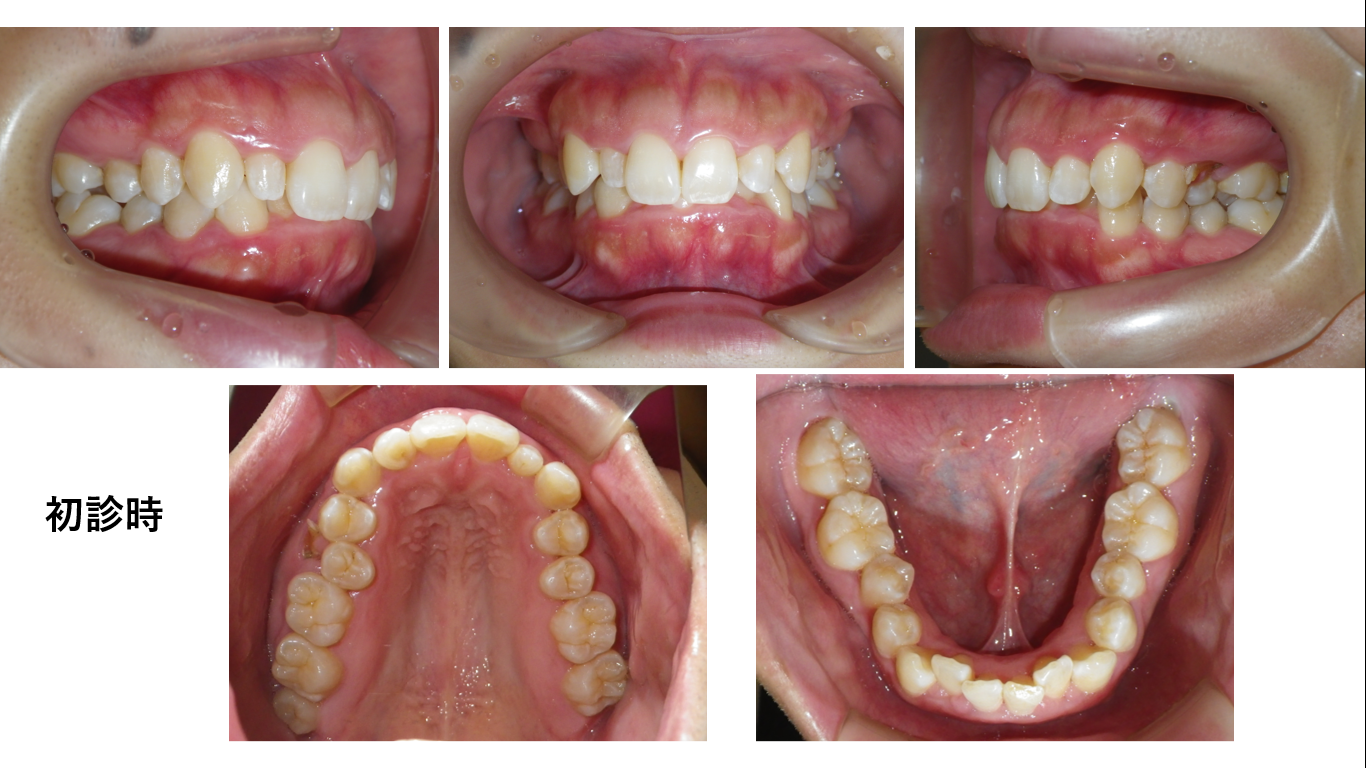

矯正症例143 AngleⅡ級2類、裏側矯正、舌側矯正

治療開始年齢24歳、治療期間3年、抜歯部位:下顎左右5番、上顎左右4番、治療費総額1,310,000(税込み)